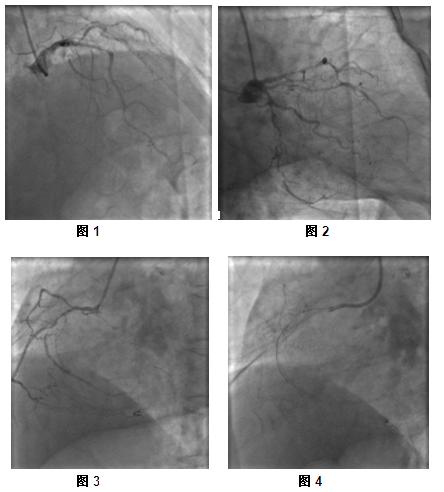

3、选择其他预扩张球囊,但通过病变处困难,最后选择选择MINI TREK球囊(1.20*6),反复尝试通过病变处,最终成功通过,以6-8ATM预扩张病变处数次(图5)。最后选择Sprinter(2.5*15)球囊,反复预扩张病变处并造影,结果如(图6)。

4、依次由远端及近端植入支架三枚,最后造影结果如(图7)。